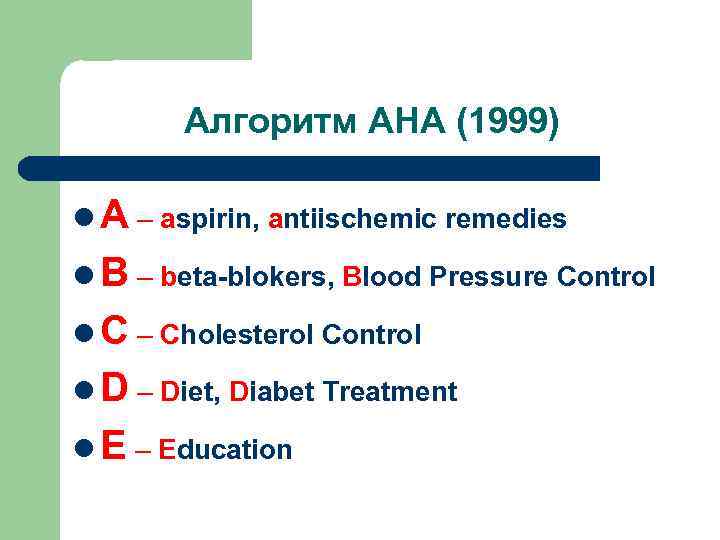

Алгоритм АНА (1999) l A – aspirin, antiischemic remedies l B – beta-blokers, Blood Pressure Control l C – Cholesterol Control l D – Diet, Diabet Treatment l E – Education